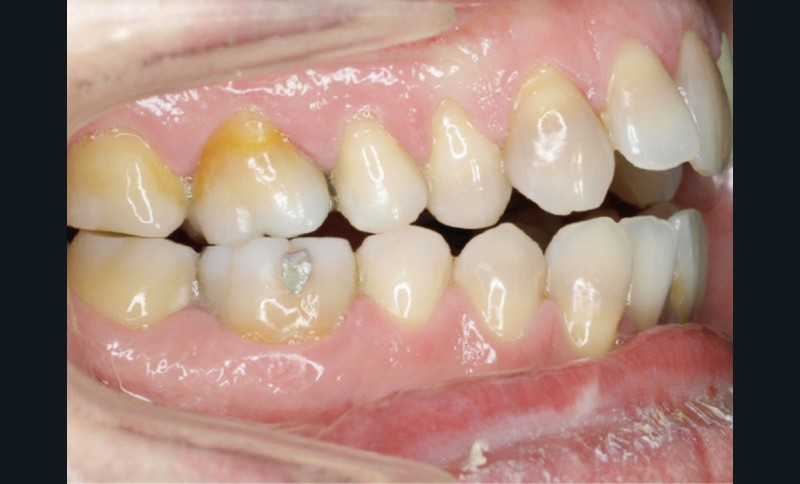

En 2008, la patiente, âgée de 34 ans, se présente pour le traitement de ses « dents mal placées, et de l’écart entre les dents du haut et du bas » (fig. 1). Elle a déjà bénéficié d’un traitement adolescent par plaque amovible maxillaire.

Au niveau exobuccal, la patiente présente un visage convexe avec un étage inférieur de la face augmenté et une absence de contact bilabial au repos traduisant un contexte dysfonctionnel. Le sourire est gingival et étroit.

L’analyse endobuccale et l’étude céphalométrique (fig. 2, tableau 1) confirment le diagnostic de classe II squelettique hyperdivergente avec une classe II molaire et canine bilatérale, associée à un encombrement, à une dysharmonie du sens transversal par endoalvéolie maxillaire, et une béance antérieure par infra-alvéolie incisive maxillaire dans un contexte dysfonctionnel de la musculature péri-labiale et mentonnière.